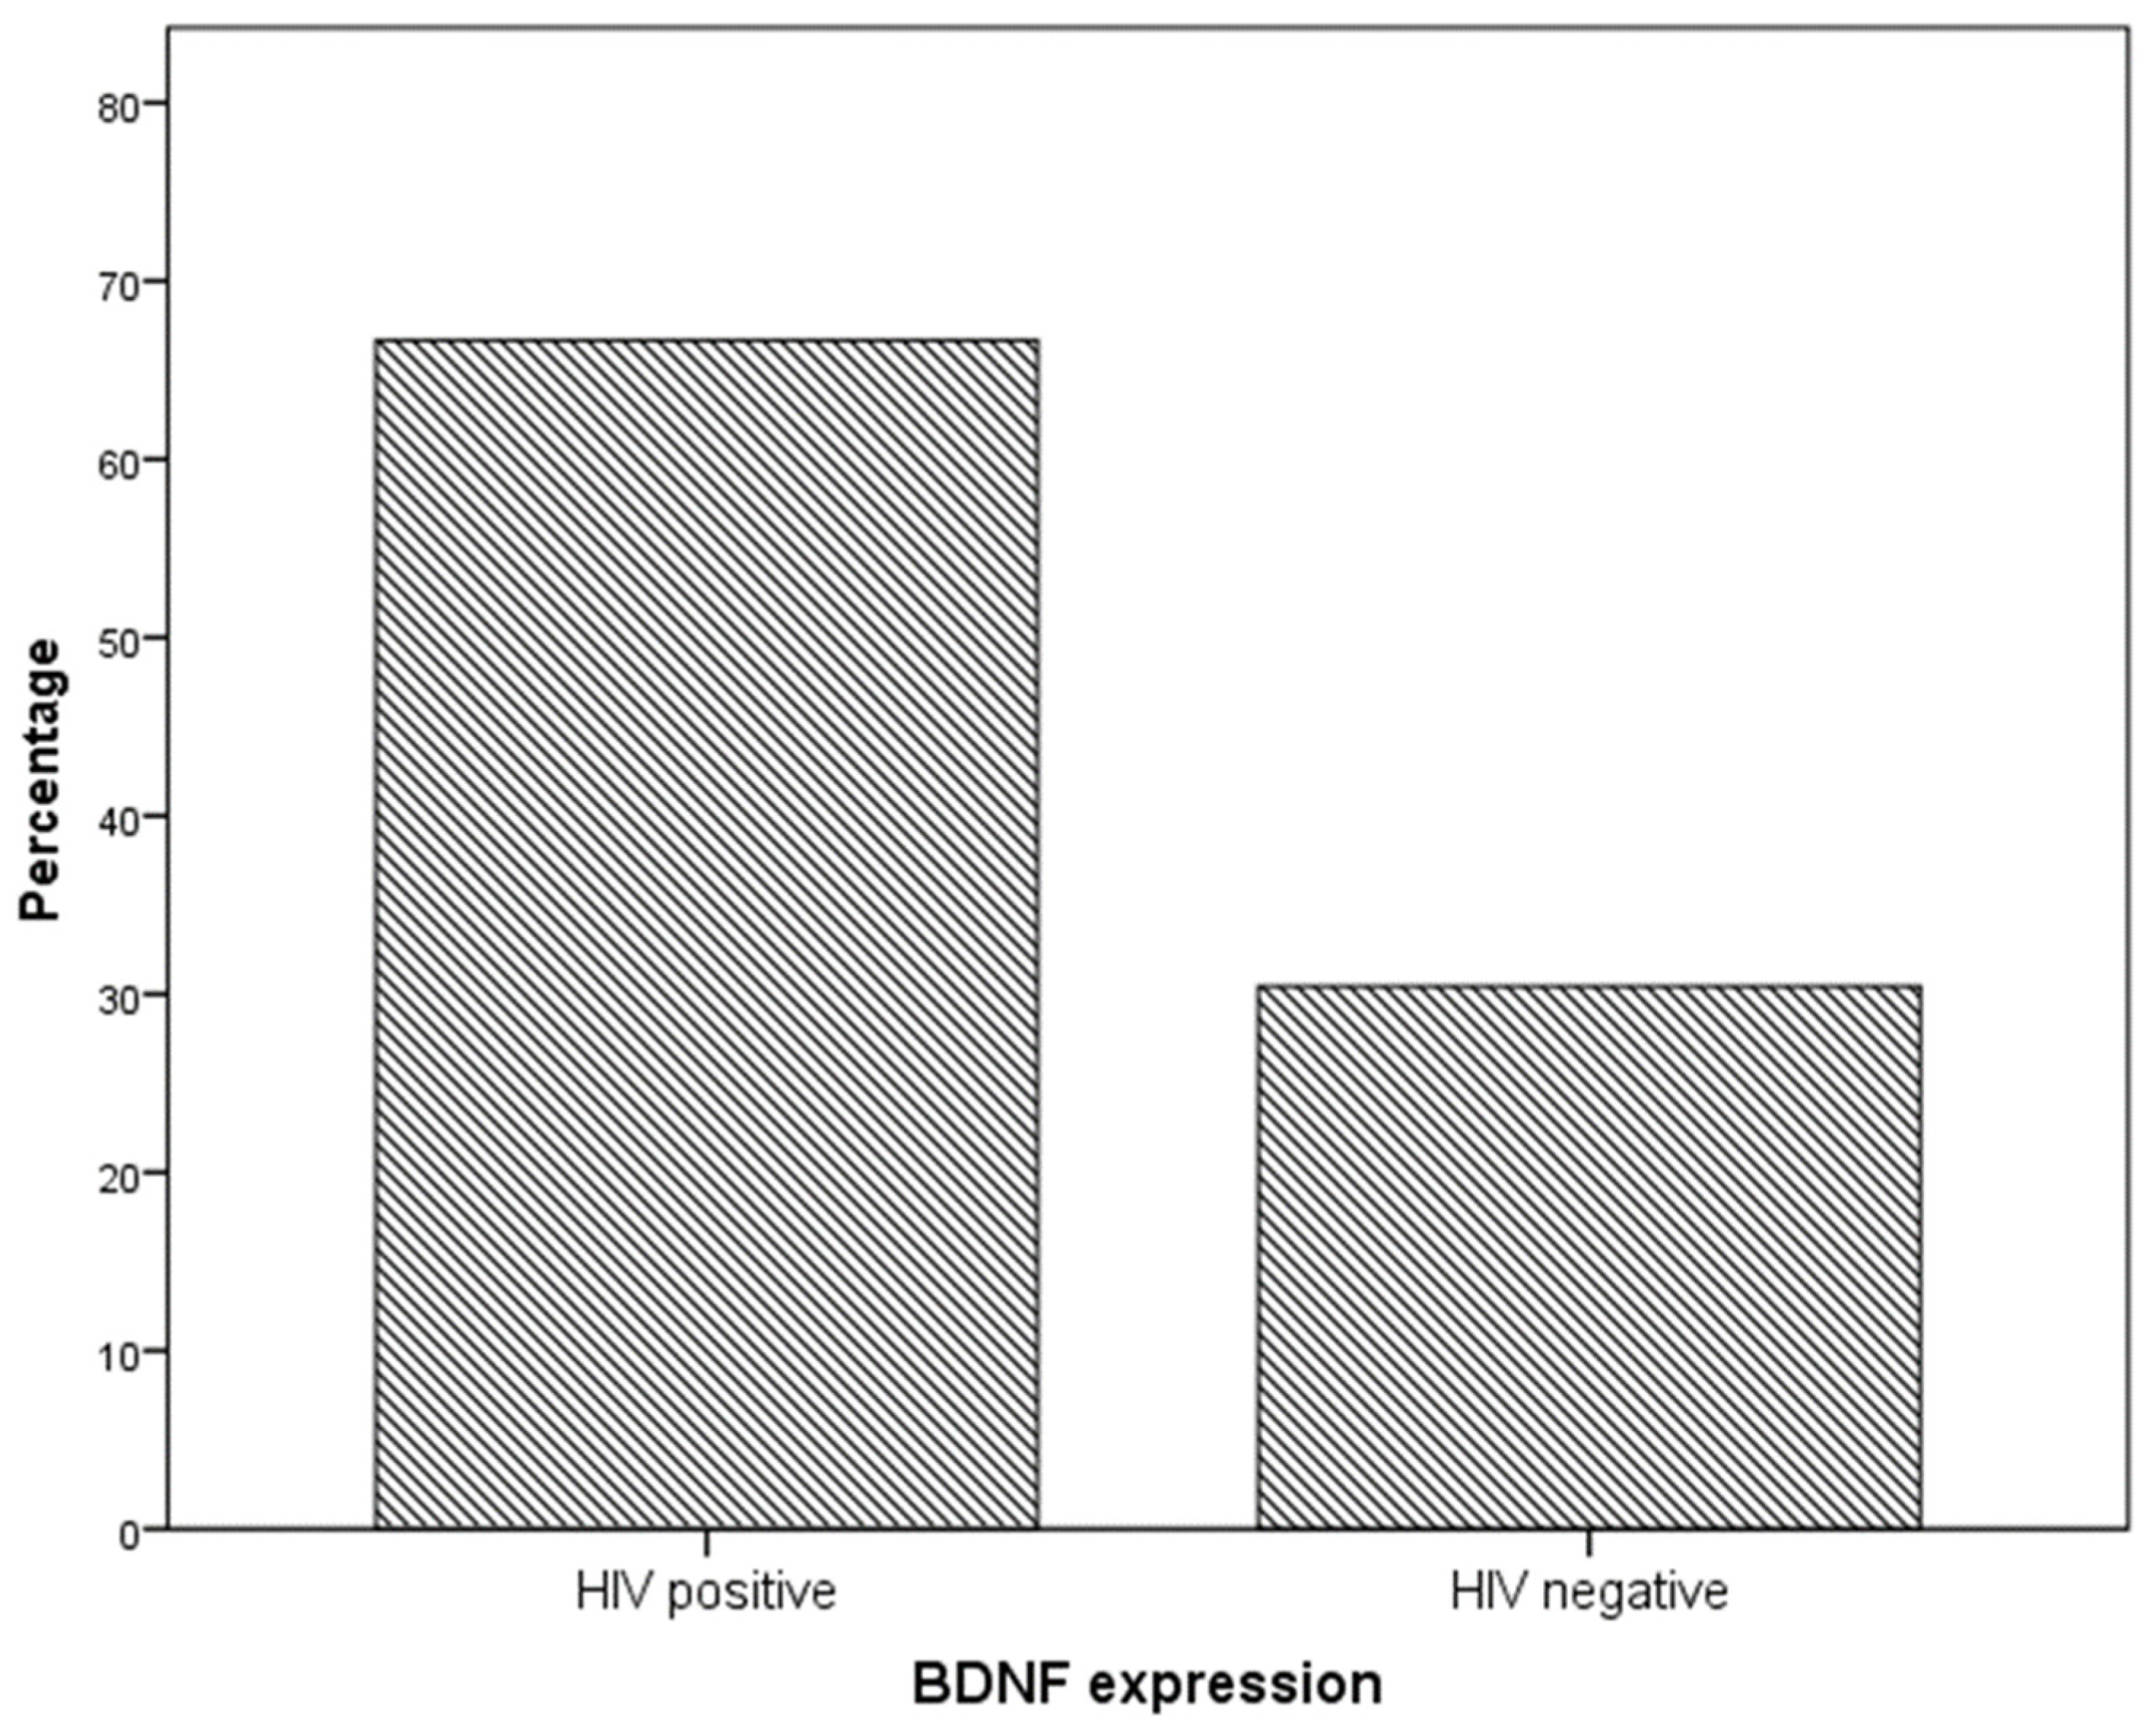

2. Results

4.1. Neurotrophin Expression in Cervical Dysplastic and Neoplastic Lesions